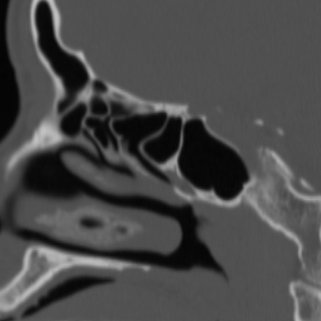

CT PNS Coronal

Click any image for labels.

You can use the mouse wheel to scroll through the images of both the sagital and coronal series.